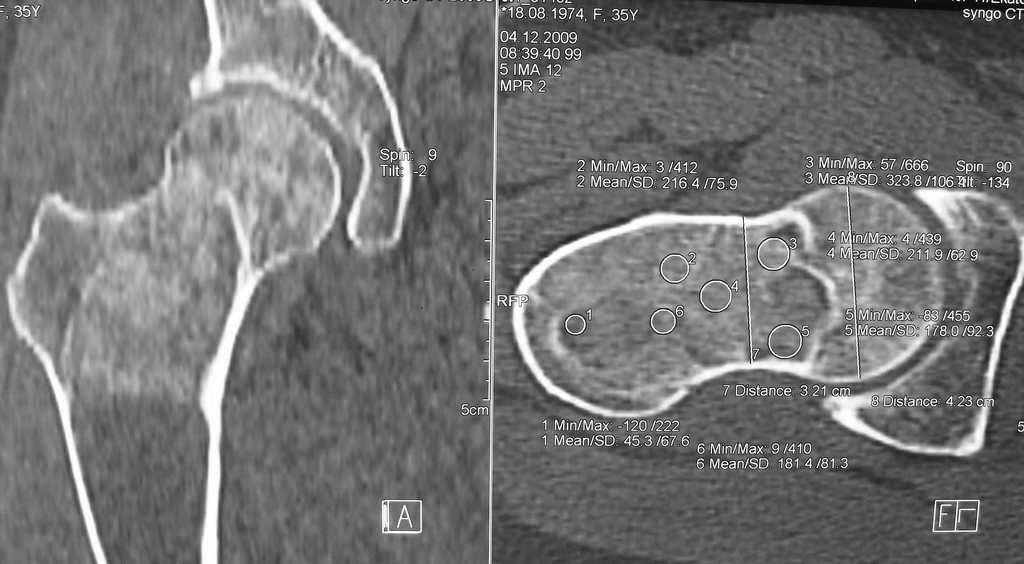

Re: Фиброзная дисплазия-продолжение